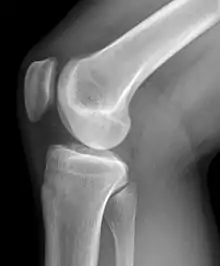

Imagerie

Il existe différentes modalités d'imagerie pour explorer la pathologie du genou. La radiographie, souvent réalisée en première intention permet d'examiner l'état des cartilages, les détachements osseux et d'éventuels bâillements en position de schuss (flexion légère). La goniométrie consiste en la réalisation d'une radiographie de l'ensemble de la jambe pour observer les déviations du genou.